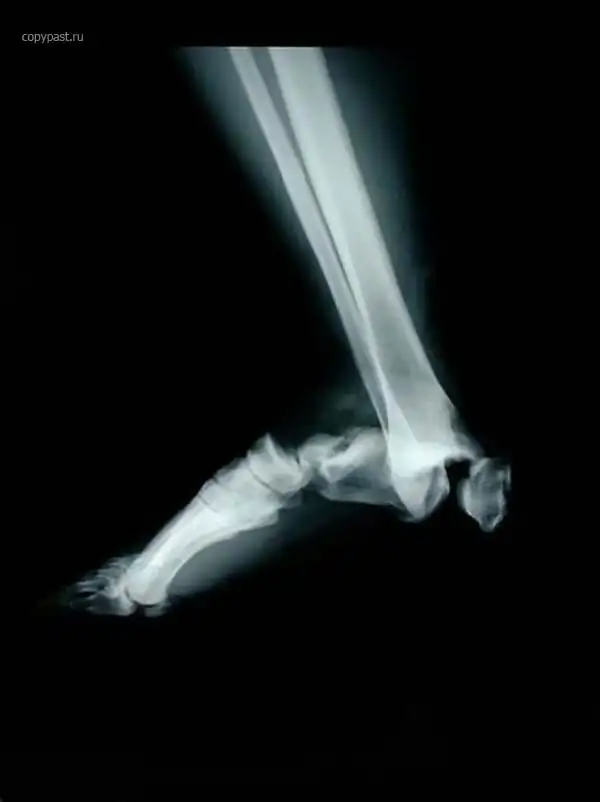

Человек сидел на переднем пассажирском сиденье в автомобиле, закинув ноги на торпеду,

в том месте, где находится подушка безопасности.

Произошла авария на скорости 40 км/ч, сработали подушки.... Вот так была сломана

ступня. Водитель не пострадал.

Я больше никогда туда не положу ноги